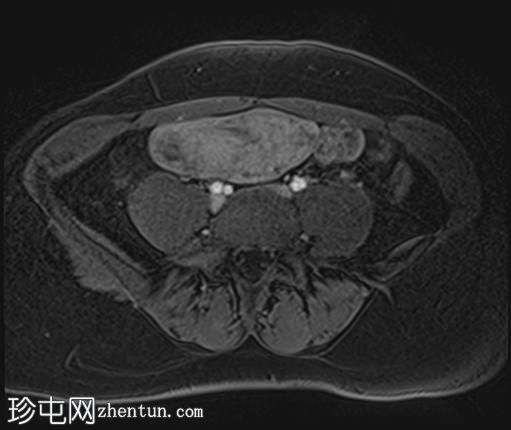

轴位T1加权像

增强脂肪抑制像

盆腔内可见多个边界清晰的肿块:

其中一个位于子宫上方,T2加权像呈中等信号,中心区域呈高信号,增强T1脂肪抑制像未见强化。右侧卵巢增大,增厚的血管蒂扭曲,未见强化,轴位和矢状位T2加权像均显示清晰。

另一个位于子宫后窝,T2加权像呈中等信号,增强扫描显示明显强化。

轻度腹腔积液